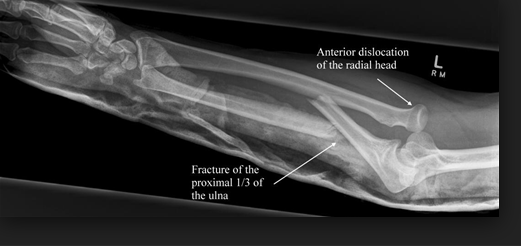

Brudd i ulnaskaftet(oftest proksimale 1/3) med samtidig dislokasjon av caput radii kalles for ………?

Og hvilken nerve er spesielt utsatt ved en slik skade?

Hvordan behandles en Monteggia-fraktur?

Gipses med laske fra MCP til aksille og opereres på sykehus.

Hvis caput radii på plass; mobilisering uten belastning 8 uker. Enkelte ganger må ligamentum annulare eksploreres og suturers preoperativt.